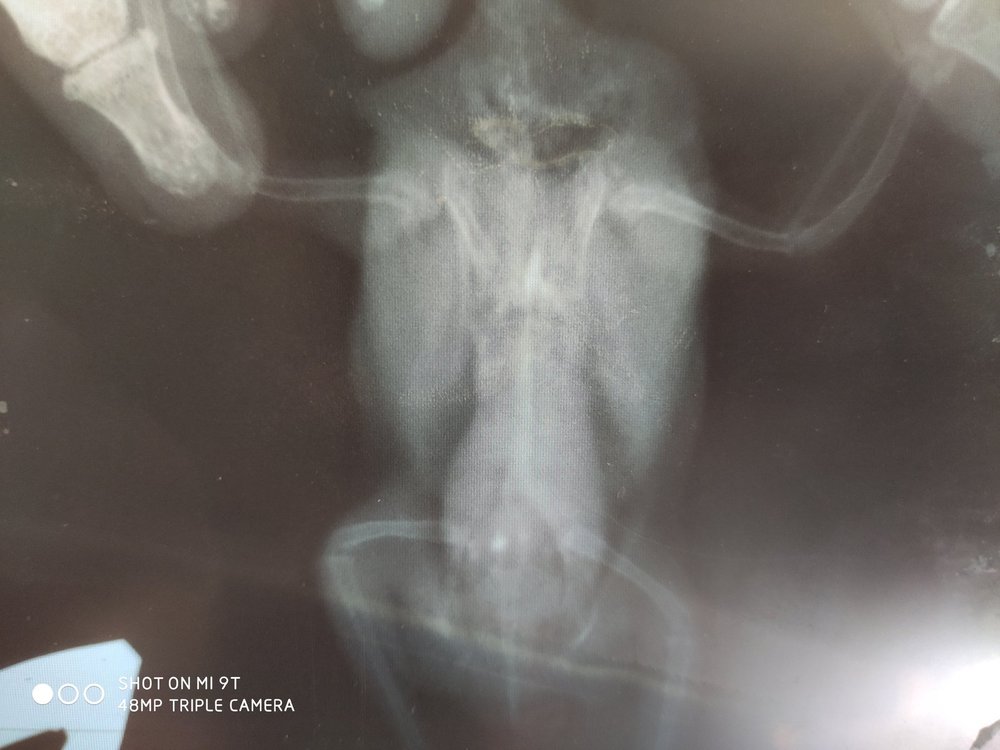

4. Какие симптомы и подробно, что случилось? В начале года сильно набирал вес (52-56 грамм), не могли похудеть, стал очень нервным, в марте неудачно упал, потерял зрение, по рентгену было видно увеличенную печень, которая давит на желудок и воздушные мешки, помет был в норме, пьем мелоксивет и габапентин постоянно, было 2 курса по месяцу Укрлива для печени, 1 курс карсила. Во время второго курса Укрлива начал какать с водой. Думали морковка плохая попалась, давали Энтеросгель отдельно от других лекарств, позже увидели, что пьет очень много воды. Изначально подумали что от голода/жадности (у него повышенный аппетит, кормили 2 ч. ложки на 7-8 приемов каждые 2 часа, 1-2раза из которых ночью). сделала глюкотест мочи - повышена.  Опускает крылья, правое ниже левого. Когда сидит скрещивает их под хвостом, когда ходит - нормально держит. Голова преимущественно наклонена влево, иногда ровно держит

Последний рентген показал ещё большее увеличение печени и почки неправильной формы. Анализ крови на глюказу -норма, мочевая кислота понижена.

Может есть ещё шансы как-то помочь ему. Рентген плёночный, засунула влажным в файл и он местами пожелтел, к сожалению. Первые два снимка - март, второй - 2 июня

К сожалению, в этой клинике рентген плёночный и для мелких птиц малоинформативен...